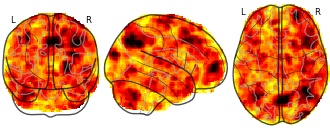

"name": "Multi_VBMsmaller_fMRIdecreased",

"description": "Multi-modal analysis in BPD. Brain regions exhibiting smaller gray matter and decreased activation during emotion processing in BPD compared to healthy controls. Note: Results were thresholded at p<.0025. Note2: Results were updated (see Erratum for this publication).",